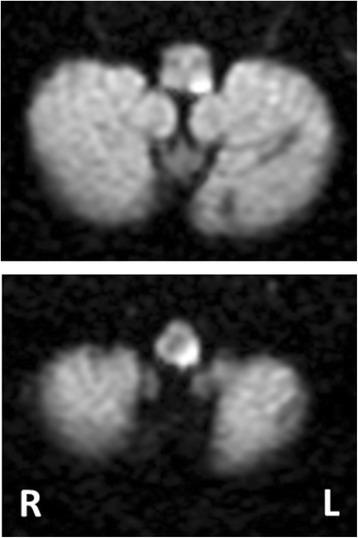

We report a case of an 86-year-old Japanese woman who developed cervical dystonia following lateral medullary infarction. She developed sudden-onset left upper and lower extremity weakness, right-side numbness, and dysarthria. Brain magnetic resonance imaging revealed an acute ischemic lesion involving the left lateral and dorsal medullae. A few days after her stroke, she complained of a taut sensation in her left neck and body, and cervico-shoulder dystonia toward the contralateral side subsequently appeared. Within a few weeks, it disappeared spontaneously, but her hemiplegia remained residual.

我们报告一例86岁日本女性,在延髓外侧梗死之后出现颈部肌张力障碍。她突发左上肢和下肢无力、右侧麻木及构音障碍。脑部磁共振成像显示急性缺血性病变累及左侧延髓外侧和背侧。中风后几天,她主诉左颈部和身体有紧绷感,随后出现向对侧的颈肩部肌张力障碍。几周内,该症状自行消失,但偏瘫仍有残留。